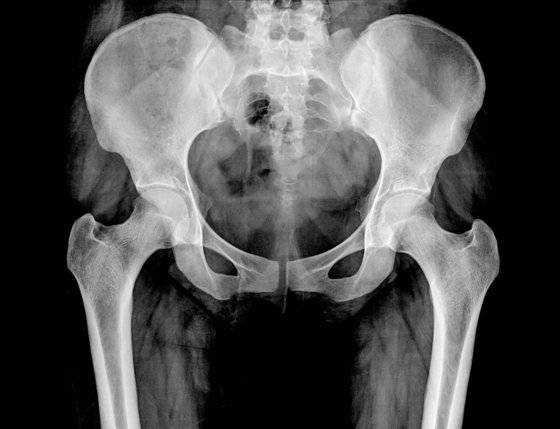

부산 서구에 있는 A 영상의학과 의원은 보험사기를 치는 이들에게는 ‘골절 작업’을 잘 해주는 병원으로 통했다. 이 병원의 의사였던 B씨가 영상 촬영만 하면 허위 골절진단서를 발급해줬기 때문이다. 환자들이 목욕탕이나 화장실에서 넘어졌다고 하면, 꼬리뼈(미추)나 엉치뼈(천골) 골절 진단을 내줬다.

양씨는 2017년 1월에 박씨의 소개로 A의원을 찾았다. 역시 “화장실에서 넘어졌다”며 허위로 꼬리뼈 골절 진단을 받은 뒤 보험금 700만원을 타냈다. 양씨는 5대 골절(목·흉추·요추·골반·대퇴골) 때 진단비 명목으로 보험금을 주는 보험 11개에 가입해 둔 상태였다.

이들 일가족은 2017년 한 해 동안 모두 목욕탕에서 넘어져나 꼬리뼈나 엉치뼈를 다쳤다며 보험금을 청구했다. 실제로는 MRI를 찍지도 않았고 골절진단서만 받았다. 이렇게 일가족이 받아낸 보험금은 총 3500만원이었다.

'보험설계사-의사-환자'로 엮인 보험사기는 2018년 4월까지 이어졌다. 이들이 보험사로부터 받아 챙긴 돈만 3억8000만원가량이다. 보험을 과다하게 많이 든 가입자로부터 꼬리뼈 골절 청구가 이어진 걸 수상하게 여긴 KB손해보험 보험사기특별조사팀(SIU)에 꼬리가 잡혔다. 보험 가입 현황 등을 조사해보니 양씨를 중심으로 보험 가입이 이어진 정황도 드러났다.

KB손보 관계자는 “골절 진단에 수가가 비싼 MRI를 주로 사용한 데다, 버스 운전을 한 가입자가 있어 허위 진단서 발급 등을 의심했다”고 말했다. KB손보 SIU는 부산경찰청 반부패수사대에 수사를 의뢰했고, 경찰은 6개월간의 수사를 통해 박씨 등의 범행을 확인했다. 병원을 압수수색에 확보한 MRI(자기공명영상촬영) 자료를 통해 골절이 없었다는 점 등을 입증했다.